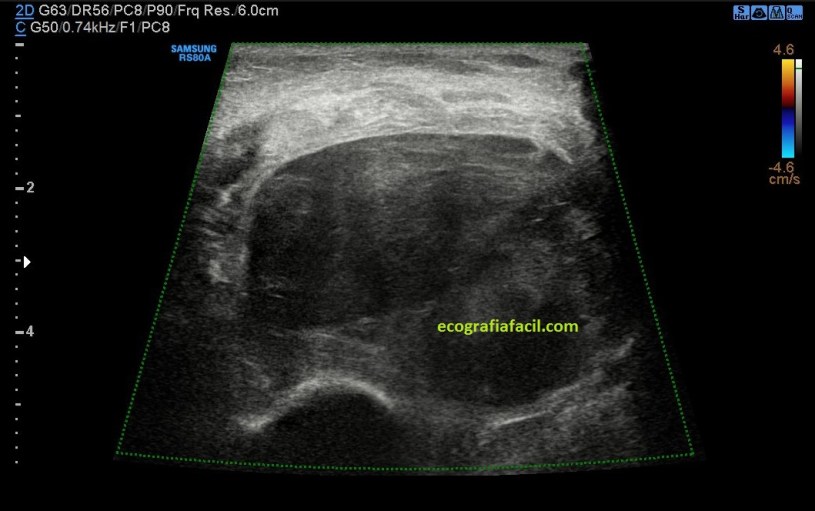

El nervio afectado por la neuropatía es avascular tanto el doppler como en el modo angio.